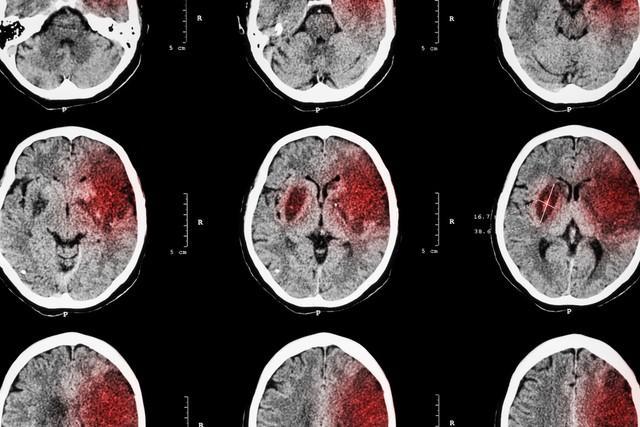

這些由於血管堵塞而出現的問題當中,腦梗死的危害遠大於其他疾病,但這種疾病所受到的關注卻遠低於其他疾病。腦梗死,也稱爲缺血性中風,是一種由大腦血液供應障礙引起的大腦疾病。

這種疾病不僅發病率高,致殘率高,而且還嚴重威脅着人們的生命健康。但是一般在腦梗死發作之前往往會有一些小小的“提示”,可以幫助我們及早發現和預防腦梗死的發生。